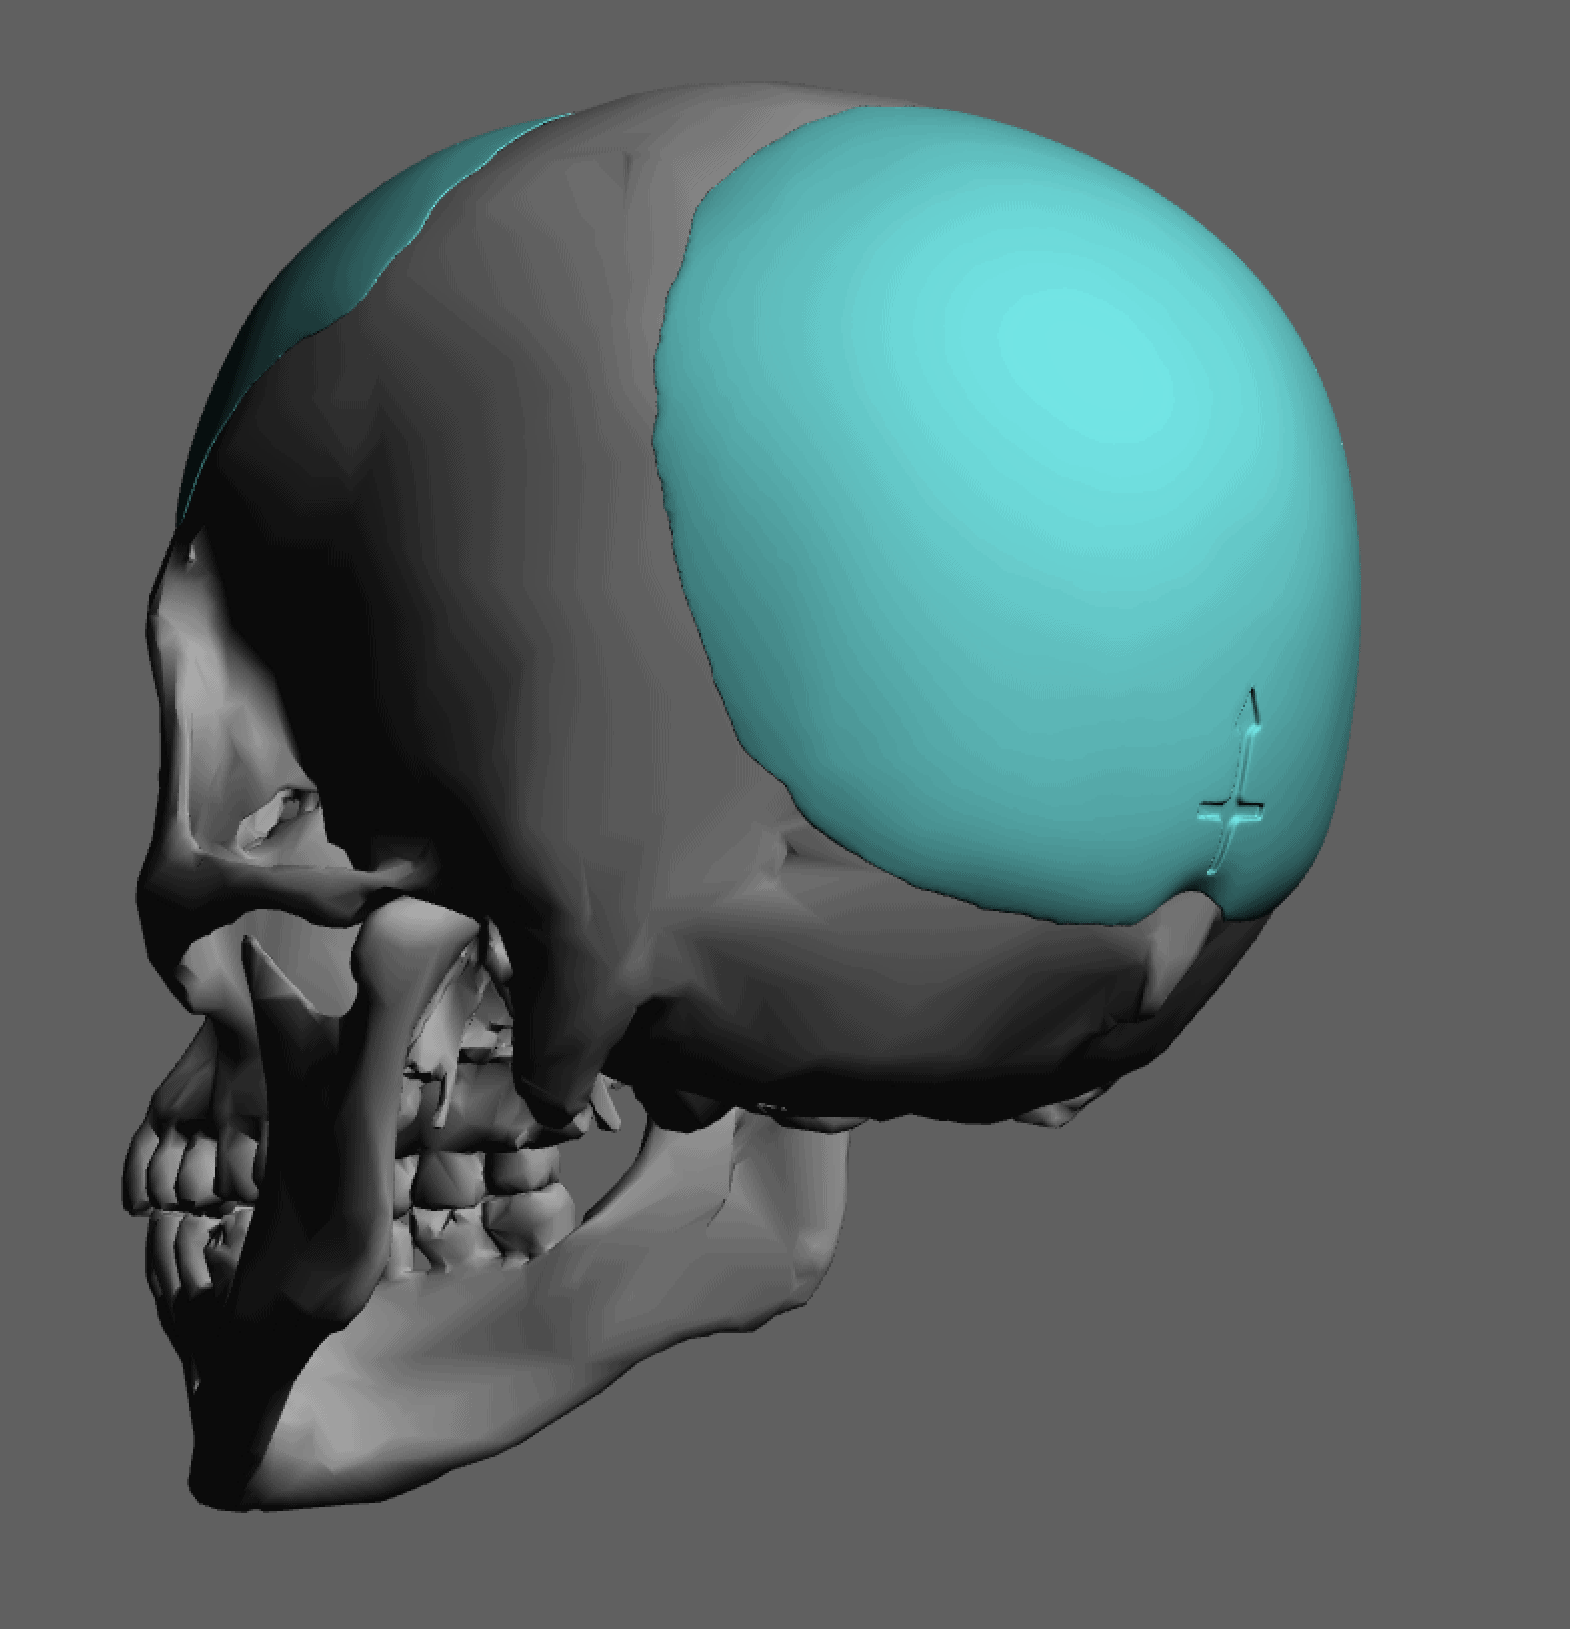

Desire for further skull augmentation after a primary skull implant.

Five years after an initial custom skull implant placement a new custom skull implant that increased the volume by 35% was placed.

Desire for further skull augmentation after a primary skull implant.

Five years after an initial custom skull implant placement a new custom skull implant that increased the volume by 35% was placed.